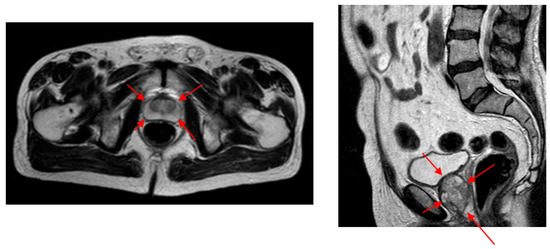

We were unable to compare our volume-estimation results with other studies as almost no other studies are available to estimate prostate volume from AUS images. Instead, we evaluated the difference in intra- and inter-expert volume estimates on AUS images and compared these values with our system estimates. Due to the higher SNR values and better image quality compared (Figure 2) to both AUS and TRUS images (Figure 1), MR image annotations are considered the gold standard [13] in prostate applications. Accordingly, we also evaluated the intra- and inter-expert volume estimation difference in MR images and compared these values with our system’s volume estimations and expert estimations on AUS images. The results show that our system achieved the volume estimate difference values of human experts.

Figure 2. The prostate contours in transverse and sagittal MR images. Due to its high SNR values, MR is accepted as the gold standard in medical image-analysis studies of the prostate.